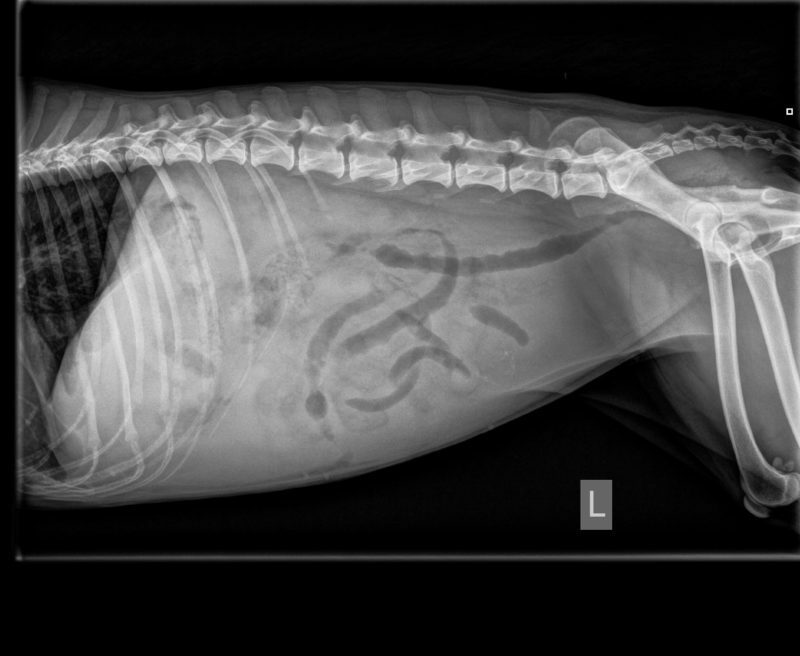

Treu ist er in dieser Zeit stets der Veterinärmedizin geblieben - und Tiermediziner nehmen in seinem neuesten Projekt, dem Onlineportal für Hundefreunde, einen wichtigen Platz ein. Mit "Hunderunden.de" gibt er Tierärzten die Möglichkeit, den Patientenbesitzern Einblick hinter die Praxiskulissen zu geben. Moll ist sich sicher, dass Menschen am liebsten Geschichten lesen und auf diese Weise auch schwierige Inhalte besser verstehen können. "Der Tierarzt als Experte kann durch seine Fallberichte einerseits Aufklärung betreiben und darüber hinaus auf eine elegante Weise Werbung in eigener Sache machen", erklärt der Portalgründer. "Wenn zum Beispiel Dr. Astrid Thelen über neueste Therapiemöglichkeiten bei Atopischer Dermatitis schreibt, oder Dr. Felix D. Sonntag (Ravensburg) erklärt, wie er den Bandscheibenvorfall bei Beagle "Quickstep" therapiert hat, sind die Leser begeistert - und sprechen auf der Hundewiese darüber.

Der Tierarzt, bzw. die Tierärztin dokumentiert einen für ihn/sie interessanten Fall und fasst diesen in für den Hundehalter veständliche Worte. Wichtig ist, dass der Patient in Wort & Bild beschrieben wird. Inhalte: Beschreibung des Patienten, Untersuchung, Diagnose, Therapie, Krankheitsverlauf. Umfang: ca. 5000 Zeichen (1-2 A4-Seiten). Bilder: Mit fünf Abbildungen kann der Beitrag gut bebildert werden.